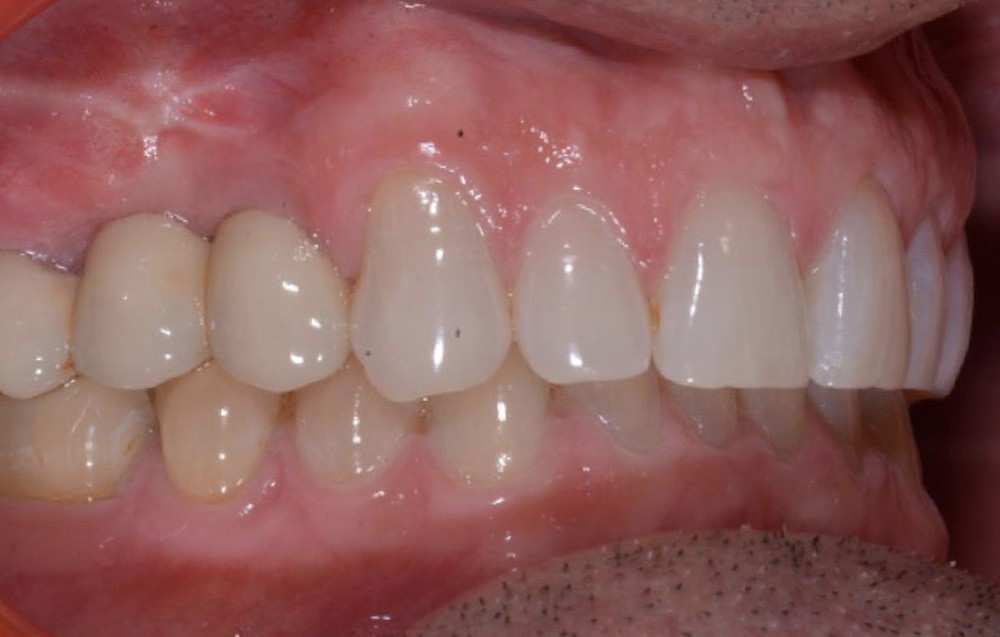

Le plan de traitement établi conjointement avec son chirurgien-dentiste traitant consiste à réaliser un alignement dentaire mandibulaire et à réaliser des extractions de 16 et 15 pour un remplacement par prothèse implanto-portée.

Les techniques orthodontiques de déplacement par gouttières orthodontiques thermoformées sont très efficaces pour gérer des situations simples. Ce patient en montre l’intérêt, en particulier lorsque la forme d’arcade dentaire doit être maintenue. Les systèmes « in-office » peuvent tout à fait permettre la gestion de ces situations.